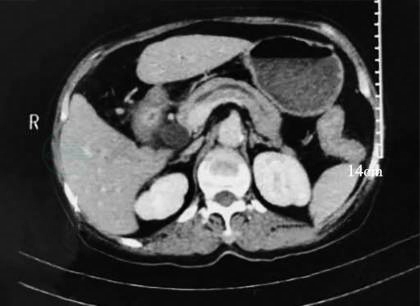

患者病情趋于稳定,遂决定进一步明确病因及病变部位。根据急诊胃镜检查的发现,患者十二指肠乳头周围存在病变,医师更加针对性地选择了超声内镜+活检检查:壶腹周围低回声灶,范围约2.0cm×1.8cm,胰头癌累及十二指肠可能。胆总管及胰管存在积血可能(图6)。病变黏膜活检结果提示为十二指肠慢性黏膜炎(图7)。为更好地判断病变与周围重要血管的关系及手术可切除性,完善肠系膜上血管计算机断层扫描静脉造影(computed tomographic venography,CTV)检查(图8),见壶腹部占位与肠系膜上动静脉存在间隙,GDA栓塞后周围水肿渗出。

图8 CTV:壶腹部低密度占位,血管间隙清。胰周渗出,胰胆系扩张。诊断:胰管积血?GDA栓塞后坏死?

2020-03-30:行腹腔镜辅助胰十二指肠切除术(改良Blumgart胰肠吻合),术中见腹腔内无明显转移结节,胰头-十二指肠周围水肿呈硬块状,范围约8cm×8cm(图9)。切除标本后,可见:壶腹部有一1.5cm×1.5cm大小肿物,侵及胰腺及十二指肠,胆管及胰管内可见陈旧性积血(图10)。术中冰冻结果:胰腺中-低分化腺癌。常规病理结果:“壶腹部”胰胆管型中低分化腺癌,大小1.5cm×1.5cm,侵及十二指肠黏膜下层、胰腺实质(图11)。神经、脉管累犯阳性,周围组织见大片液化坏死伴肉芽组织增生。淋巴结2/18。pTNM分期T3aN1M0。免疫组化:CK7(-)、CK20(-)、CDX2(弱+)、P53(突变型)、Ki-67(约30%)。

图9 胰头-十二指肠周围水肿明显